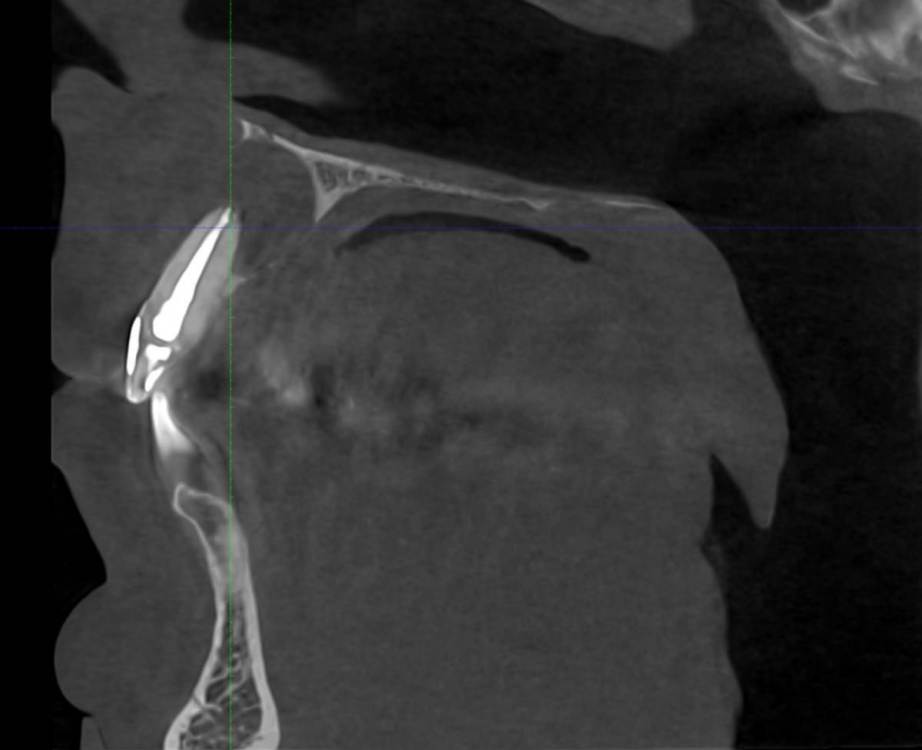

feGTX Опубликовано 15 июля, 2022 Поделиться Опубликовано 15 июля, 2022 (изменено) Здравствуйте. Очень нужна помощь стоматологов! В 2019 году обнаружил свищ над верхними передними зубами. Пошел к своему стоматологу, который начал следующее лечение: - нервы в зубах были удалены и пару дней я ходил с открытым каналом. Далее закладывался Метапекс, а потом постоянная пломба, но свищ не закрылся. 22 зуб также залечили. Были консультации и в других стоматологиях нашего маленького городка (КТ тогда тоже делалось), но в основном рекомендовали три зуба под удаление, закладывание искусственной кости, импланты или мосты на соседние зубы. Решили пробовать перелечивать со своим стоматологом. - 21 зуб снова вскрыли и несколько раз закладывали Кальцетин. Потом снова постоянная пломба. И свищ закрылся (это было осенью 2019 года). Далее делали несколько снимков - вроде медленно шло заживление. В сентябре 2021 года делал КТ нижней челюсти по другой проблеме, и захватилась верхняя челюсть - тоже были видны улучшения в сравнении с самой первой КТ. И вот на днях снова свищ на десне. Надавливаю под носом и выходит жидкость. Снимок сделали, но как-то коряво вышел он. Сделал также КТ. Снова всё плохо. Во вложении три старых снимка, один свежий, и несколько изображений с КТ. Если нужны еще какие-то срезы, то попробую сделать. Помогите пожалуйста. Изменено 15 июля, 2022 пользователем feGTX Ссылка на комментарий

АнтонТЛТ Опубликовано 27 сентября, 2024 Поделиться Опубликовано 27 сентября, 2024 Ну как-то так прошла операция, резекция трёх зубов, 3д реконструкции последнего кт нет в телефоне Дефект сквозной был 6 Ссылка на комментарий